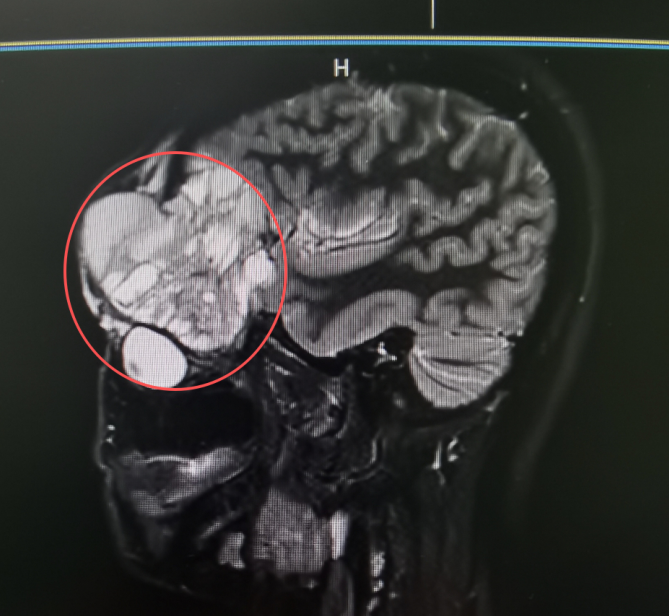

入院时影像检查显示:肿瘤沿上颌骨向上浸润性生长,侵犯至眼眶,推挤眼球并累及眶尖重要结构,进一步攀升至颅底,紧贴守护大脑的“最后屏障”——硬脑膜。

手术需在视觉神经与大脑交界处进行毫米级操作,稍有不慎,就可能引发严重并发症,治疗难度极大。